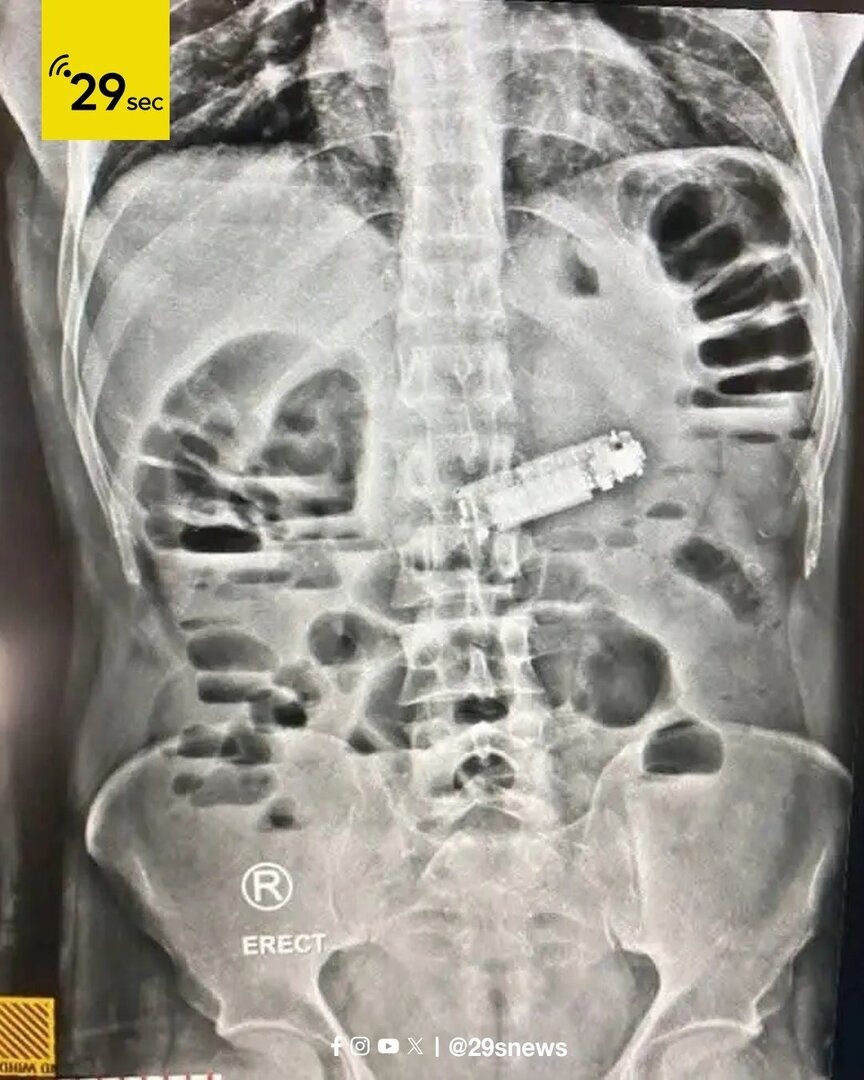

وأجرى الفريق الطبي جراحة استغرقت ساعتين نجحوا خلالها في استخراج الهاتف دون أضرار للأعضاء، والمريض حالته مستقرة ويخضع للمراقبة الطبية، في حين لم تُكشف أسباب ابتلاع الهاتف.